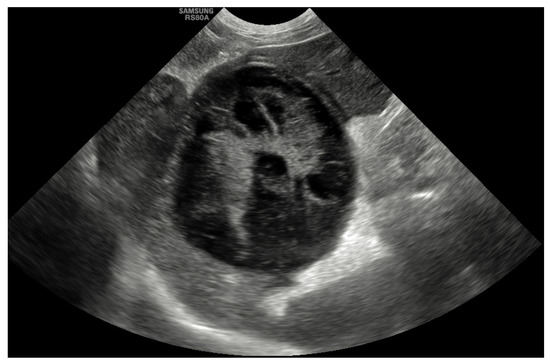

Abdominal ultrasound was the most common diagnostic tool used to diagnose GBM and was performed in all cases (100%). The most common abnormality that was described in 45 dogs (55%) was evidence of a GBM with a stellate or so-called “kiwi-fruit” pattern (Figure 1). A combination of a distended and thick gallbladder with hyperechoic and organized bile sediment compatible with an early GBM was described in the other 37 cases (45%). Hyperechoic pericholecystic fat was described in 11 dogs, and free peritoneal fluid was reported in 7 dogs. Other findings included hepatomegaly (15%), congenital extrahepatic portosystemic shunt (EHPSS; 2.5%), liver nodules (7%), splenic nodules (1.2%), bilateral adrenal gland enlargement (1.2%) and bladder nodules (1.2%). The common bile duct was considered to be within the normal limits (<4 mm) in 72 dogs (88%), mildly dilated (5–6 mm) in 8 dogs (10%) and moderately dilated (>7 mm) in 2 dogs (2.4%). The intrahepatic ducts were considered normal in all cases.

Figure 1. Sagittal ultrasonographic image of a gall bladder mucocele with multiple hyperechoic areas with a stellate appearance in an 8-year-old female neutered border terrier.